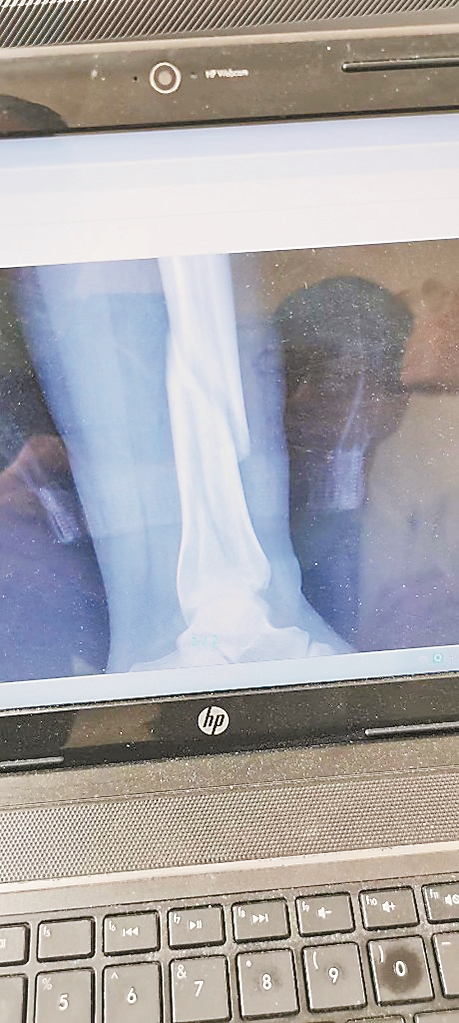

随后,在商场工作人员的帮助下,刘先生将爱人送至哈尔滨市第五医院救治。经医生诊断为左侧胫腓骨远端骨折。1月9日,刘先生爱人做了手术,1月14日出院,前后花费了近三万元。刘先生说:“一年后还要再做一次手术,将固定腿部的钢板取出,还需要两万元左右。我多次找到哈尔滨麦德龙商场交涉,他们总是推脱称,得向总部汇报。关于救治伤者费用和赔偿问题,一直到现在也没给解决。”